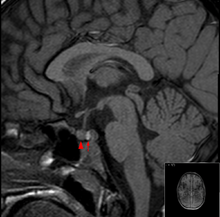

The diagnosis is achieved with magnetic resonance imaging and blood tests. Treatment is by the timely correction of hormone deficiencies, and in many cases surgical decompression is required. Many people who have had a pituitary apoplexy develop pituitary hormone deficiencies and require long-term hormone supplementation. The first case of the disease was recorded in 1898.[1]

It is recommended that magnetic resonance imaging (MRI) scan of the pituitary gland is performed if the diagnosis is suspected; this has a sensitivity of over 90% for detecting pituitary apoplexy; it may demonstrate infarction (tissue damage due to a decreased blood supply) or hemorrhage.[1] Different MRI sequences can be used to establish when the apoplexy occurred, and the predominant form of damage (hemorrhage or infarction).[2] If MRI is not suitable (e.g. due to claustrophobia or the presence of metal-containing implants), a computed tomography (CT) scan may demonstrate abnormalities in the pituitary gland, although it is less reliable.[1] Many pituitary tumors (25%) are found to have areas of hemorrhagic infarction on MRI scans, but apoplexy is not said to exist unless it is accompanied by symptoms.[1][4]